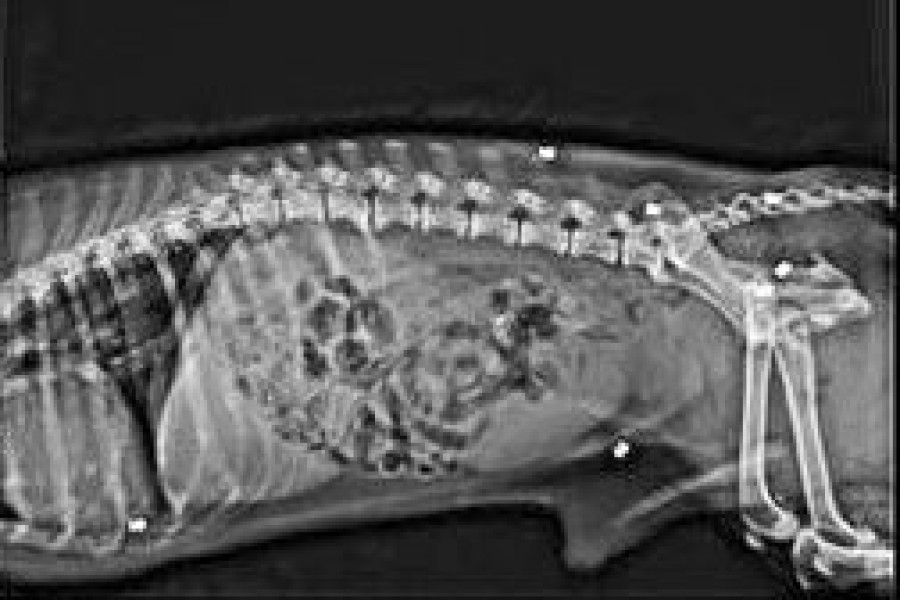

Ustalono, że psiak został postrzelony sześciokrotnie. Co więcej, zwyrodnialec musiał strzelać do zwierzęcia z bliska (śrut utkwił głęboko w ciele).